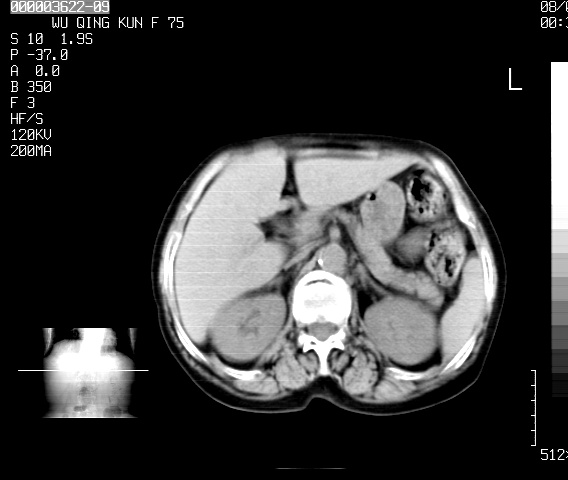

以下是引用卜一在2008-5-20 2:45:00的发言:[br]与胃腔关系密切,胃壁增厚不明显,建议行胃镜或钡餐内检查!

以下是引用dyqct在2008-5-20 10:49:00的发言:[br][quote]以下是引用卜一在2008-5-20 2:45:00的发言:[br]与胃腔关系密切,胃壁增厚不明显,建议行胃镜或钡餐内检查!